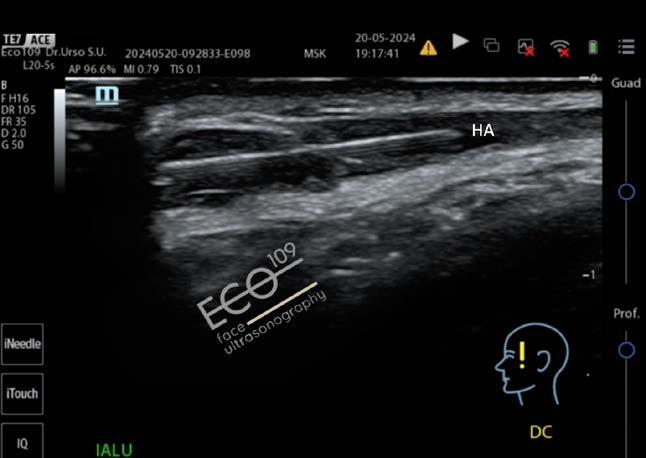

L’ecografia del volto nella Medicina Estetica avanzata